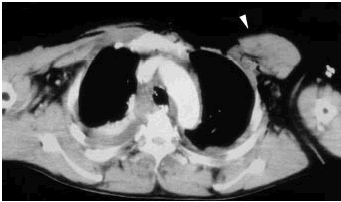

La palpación detectó un espacio vacío en la región infraclavicular izquierda. Se realizó una TC de tórax al ingreso, que puso de manifiesto la presencia de una contusión pulmonar izquierda con derrame pleural bilateral, y en la pared torácica una desinserción del músculo pectoral mayor izquierdo en su unión con la articulación condrosternal, con retracción lateral del vientre del músculo.